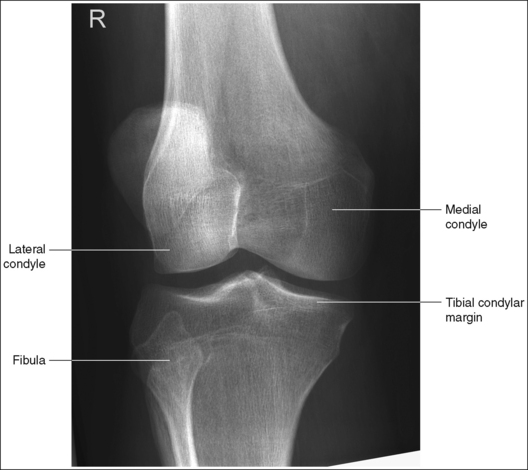

The knee demonstrates an AP projection. The medial and lateral femoral epicondyles are in profile, the femoral condyles are symmetrical, the intercondylar eminence is centered within the intercondylar fossa, and the tibia is superimposed over 0.25 inch (0.6 cm) of the fibular head.

• To obtain an AP knee projection, place the patient in a supine position with the knee fully extended. Internally rotate the leg until an imaginary line drawn between the medial and lateral femoral epicondyles is positioned parallel with the IR (Figure 6-71). This positioning places the medial and lateral femoral epicondyles at equal distances from the IR as well as medially and laterally in profile, respectively. It also centers the intercondylar eminence within the intercondylar fossa and draws the fibular neck and a portion of the fibular head from beneath the tibia.

• Effect of rotation. If the femoral epicondyles are not positioned parallel with the IR, an AP projection has not been obtained. If the patient's leg was not internally rotated enough to place the epicondyles at equal distances from the IR, they are not in profile, the medial femoral condyle appears larger than the lateral condyle, and the tibia is superimposed over more than 0.25 inch (0.6 cm) of the fibular head (see Image 54). If the patient's leg was internally rotated more than needed to place the femoral epicondyles at equal distances from the IR, the epicondyles are not demonstrated in profile, the lateral femoral condyle appears larger than the medial condyle, and the tibia is superimposed over less than 0.25 inch (0.6 cm) of the fibular head (see Image 55).

The knee joint space is open, the anterior and posterior condylar margins of the tibia are superimposed, the intercondylar eminence and tubercles are demonstrated in profile, and the fibular head is demonstrated approximately 0.5 inch (1.25 cm) distal to the tibial plateau.

• The anterior and posterior condylar margins of the tibia are superimposed if the correct central ray angulation, as determined by the patient's upper thigh and buttocks thickness, is used. By studying the tibial plateau region, you will see that the tibial plateau slopes distally approximately 5 degrees from the anterior condylar margin to the posterior condylar margin on both the medial and lateral aspects (Figure 6-72). Only if the central ray is aligned parallel with the tibial plateau slope is an open knee joint space obtained.

• Analysis of joint space narrowing. On an AP knee projection with adequate positioning, joint space narrowing is evaluated by measuring the medial and lateral aspects of the knee joint, which are also referred to as compartments. The measurement of each of these compartments is obtained by determining the distance between the most distal femoral condylar surface and the posterior condylar margin of the tibia on each side. Comparison of these measurements with each other, with measurements from previous images, or with measurements of the other knee determines joint space narrowing or a valgus or varus deformity. In a valgus deformity the lateral compartment is narrower than the medial compartment; in a varus deformity the medial compartment is narrower (see Images 56 and 57). Precise measurements of the compartments are necessary to ensure early detection of joint space narrowing and are best obtained when the knee joint space is completely open. If an inaccurate central ray angulation was used for an AP knee projection, the knee joint is narrowed or obscured, the intercondylar eminence and tubercles are foreshortened, and the tibial plateau is demonstrated.